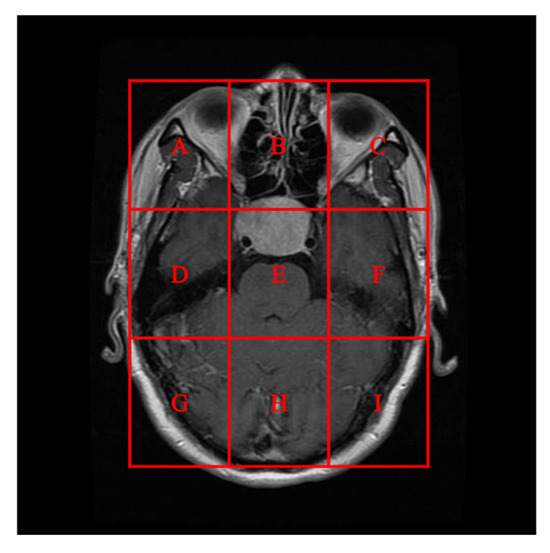

To better align our VUF-MIWS with the practical needs of clinicians for authenticating medical image sources, we conducted a pilot interview at a regional hospital. In this interview, we defined the critical diagnostic reference area of a medical image as the ROI (Region of Interest) and divided it into nine sub-regions, as shown in Figure 14. We then asked seven doctors to indicate their two most preferred locations for visible watermarks. Based on the collected feedback, sub-region A received the highest number of votes (a total of nine), followed by sub-regions E and I (both receiving five votes). Therefore, sub-region A was selected as the watermark position for the first and second experiments. The resulting watermarked images for the first experiments are displayed in Figure 15.

Figure 14. In the first and second experiments, nine sub-regions were designated as position candidates for the visible watermark.